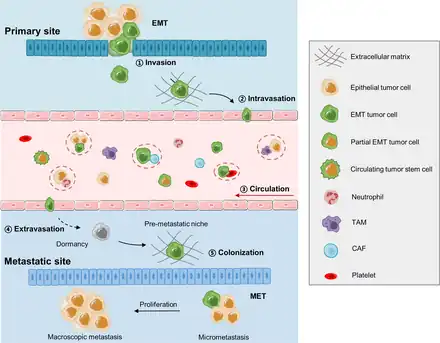

Permettre l’évasion des cellules et la formation de métastase

Une fois la tumeur primitive formée, le processus en plusieurs étapes d'invasion et de métastases se produit. La combinaison des processus qui conduisent à l'invasion des cellules tumorales et à la formation et à la colonisation de métastases est complexe, il existe donc de nombreuses hypothèses. concernant leur fonctionnement et leur importance[18]. Il a été démontré que certains cancers peuvent métastaser à des stades précoces de la maladie ; les micro-métastases peuvent se disperser à partir de tumeurs de nature non invasive et la faible capacité à retenir les cellules cancéreuses dans leur système sanguin/lymphatique entraîne une invasion plus facile du parenchyme[44],[45].

Formation d'une métastase

La formation d'une métastase est un processus comportant plusieurs étapes.

- Les cellules cancéreuses doivent se transformer pour se détacher et pouvoir traverser les parois des vaisseaux. Elles doivent devenir plus résistantes. Cette transformation s'appelle la transition épithélio-mésenchymateuse. (Passage du jaune au vert dans la figure)

- La cellule tumorale ainsi transformée peut traverser la paroi d'un vaisseau. Cette traversée s'appelle intravasation.

- La cellule tumorale est dans le sang. Elle est appelée cellule tumorale circulante. Elle est accompagnée de plusieurs cellules qui la protège(macrophage, fibroblaste, plaquette). Certaines cellules accompagnatrices viennent aussi de la tumeur.

- La cellule tumorale traverse la paroi quand elle trouve un organe près à l’accueillir : c'est l'extravastion.

- En fait, cet organe a reçu avant des signaux et matériaux de la tumeur grâce à des microvésicules pour préparer l’accueil des cellules : c'est la niche pré métastatique. Elle prépare le terrain notamment en formant de nouveau

- Une fois arrivée dans la niche métastatique, la cellule redevient une cellule cancéreuse par le processus inverse c'est la transition mésenchymato-épithéliale